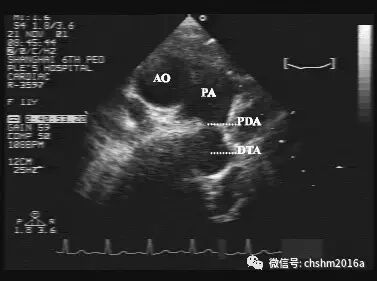

1.M型和二维超声心动图

主动脉根部短轴切面可见主肺动脉分叉处有异常通路与降主动脉相贯通,这异常的通路即为未见的动脉导管,并可显示导管的形态、粗细及长度。肺动脉主干及其分支扩张,左房、左室扩大。

彩超伪像是什么先天性心脏病超声诊断(超声梦影像医生集团 CCM)_https://www.jmylbn.com_新闻资讯_第10张

图2.3.8   大动脉短轴见肺动脉分叉与降主动脉有一管型连接

PA:肺动脉   AO:主动脉   PDA:动脉导管未闭   DTA:胸主动脉